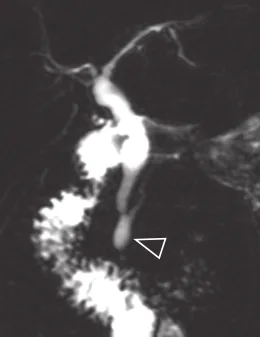

Figure 2.

A. Acquisition 3D de bili-IRM. Chez ce patient à la respiration irrégulière, l’échec de la synchronisation respiratoire (nécessaire à l’acquisition de cette séquence) rend dans ce cas les images quasi ininterprétables.

B. Ici, c’est une coupe épaisse 2D acquise lors d’une courte apnée qui s’avère plus contributive pour montrer l’empierrement cholédocien (têtes de flèches)